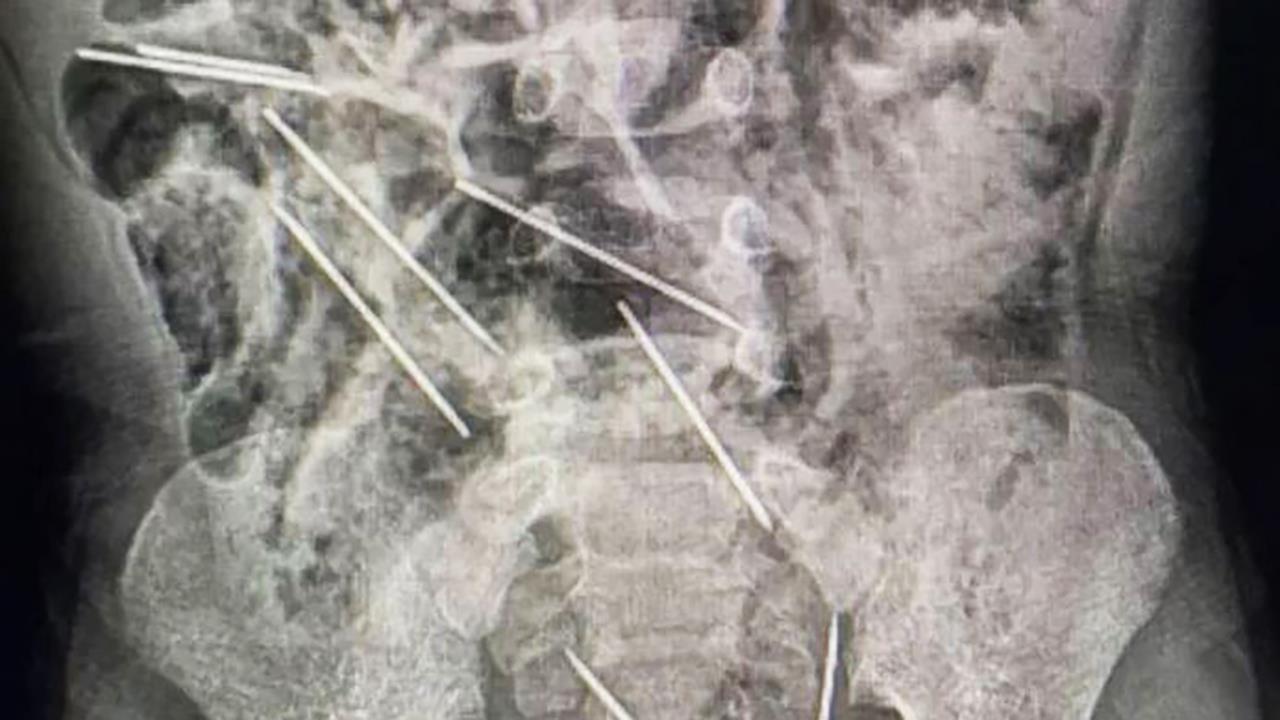

Μόλις συνειδητοποίησε τη σοβαρότητα της κατάστασης, το αγόρι μεταφέρθηκε γρήγορα στο νοσοκομείο II-2 Tarapoto, όπου ο δρ Efrain Salazar ηγήθηκε της χειρουργικής ομάδας. Κατά τη διάρκεια της διαδικασίας, διαπιστώθηκε ότι οι βελόνες είχαν σφηνώσει σε διάφορα σημεία της κοιλιάς του αγοριού, αποτελώντας σημαντική απειλή για την υγεία του.

Σύμφωνα με ανακοίνωση της περιφερειακής κυβέρνησης του San Martin, οι βελόνες βρέθηκαν σε δύο θέσεις στο περιτόναιο στη δεξιά πλευρά, τρεις στην αριστερή πλευρά, μία στο κοιλιακό τοίχωμα και δύο σε επικίνδυνη θέση μεταξύ της ουροδόχου κύστης και του ορθού.

Ευτυχώς, η επέμβαση στέφθηκε με επιτυχία, καθώς και οι οκτώ βελόνες αφαιρέθηκαν με ασφάλεια κατά τη διάρκεια μιας επέμβασης δύο ωρών. Η ιατρική ομάδα αντιμετώπισε επίσης μικρές βλάβες στο λεπτό έντερο του παιδιού που προκλήθηκαν από τα αιχμηρά αντικείμενα.